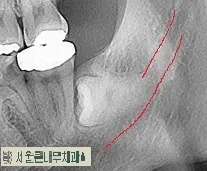

사랑니 충치에 의한 손상으로 앞치아까지 충치가 진행되었다면 고민없이 사랑니 발치를 진행하면 됩니다.

사랑니 발치이후 인접치에 영향을 주어 충치로 인해 썩어있는 모습입니다.

발치 시기를 놓쳐 충치가 많이 진행된 모습이며 비용도 추가로 더 들기 때문에 미리 예방차원에서도 발치하는 것을 권유합니다.